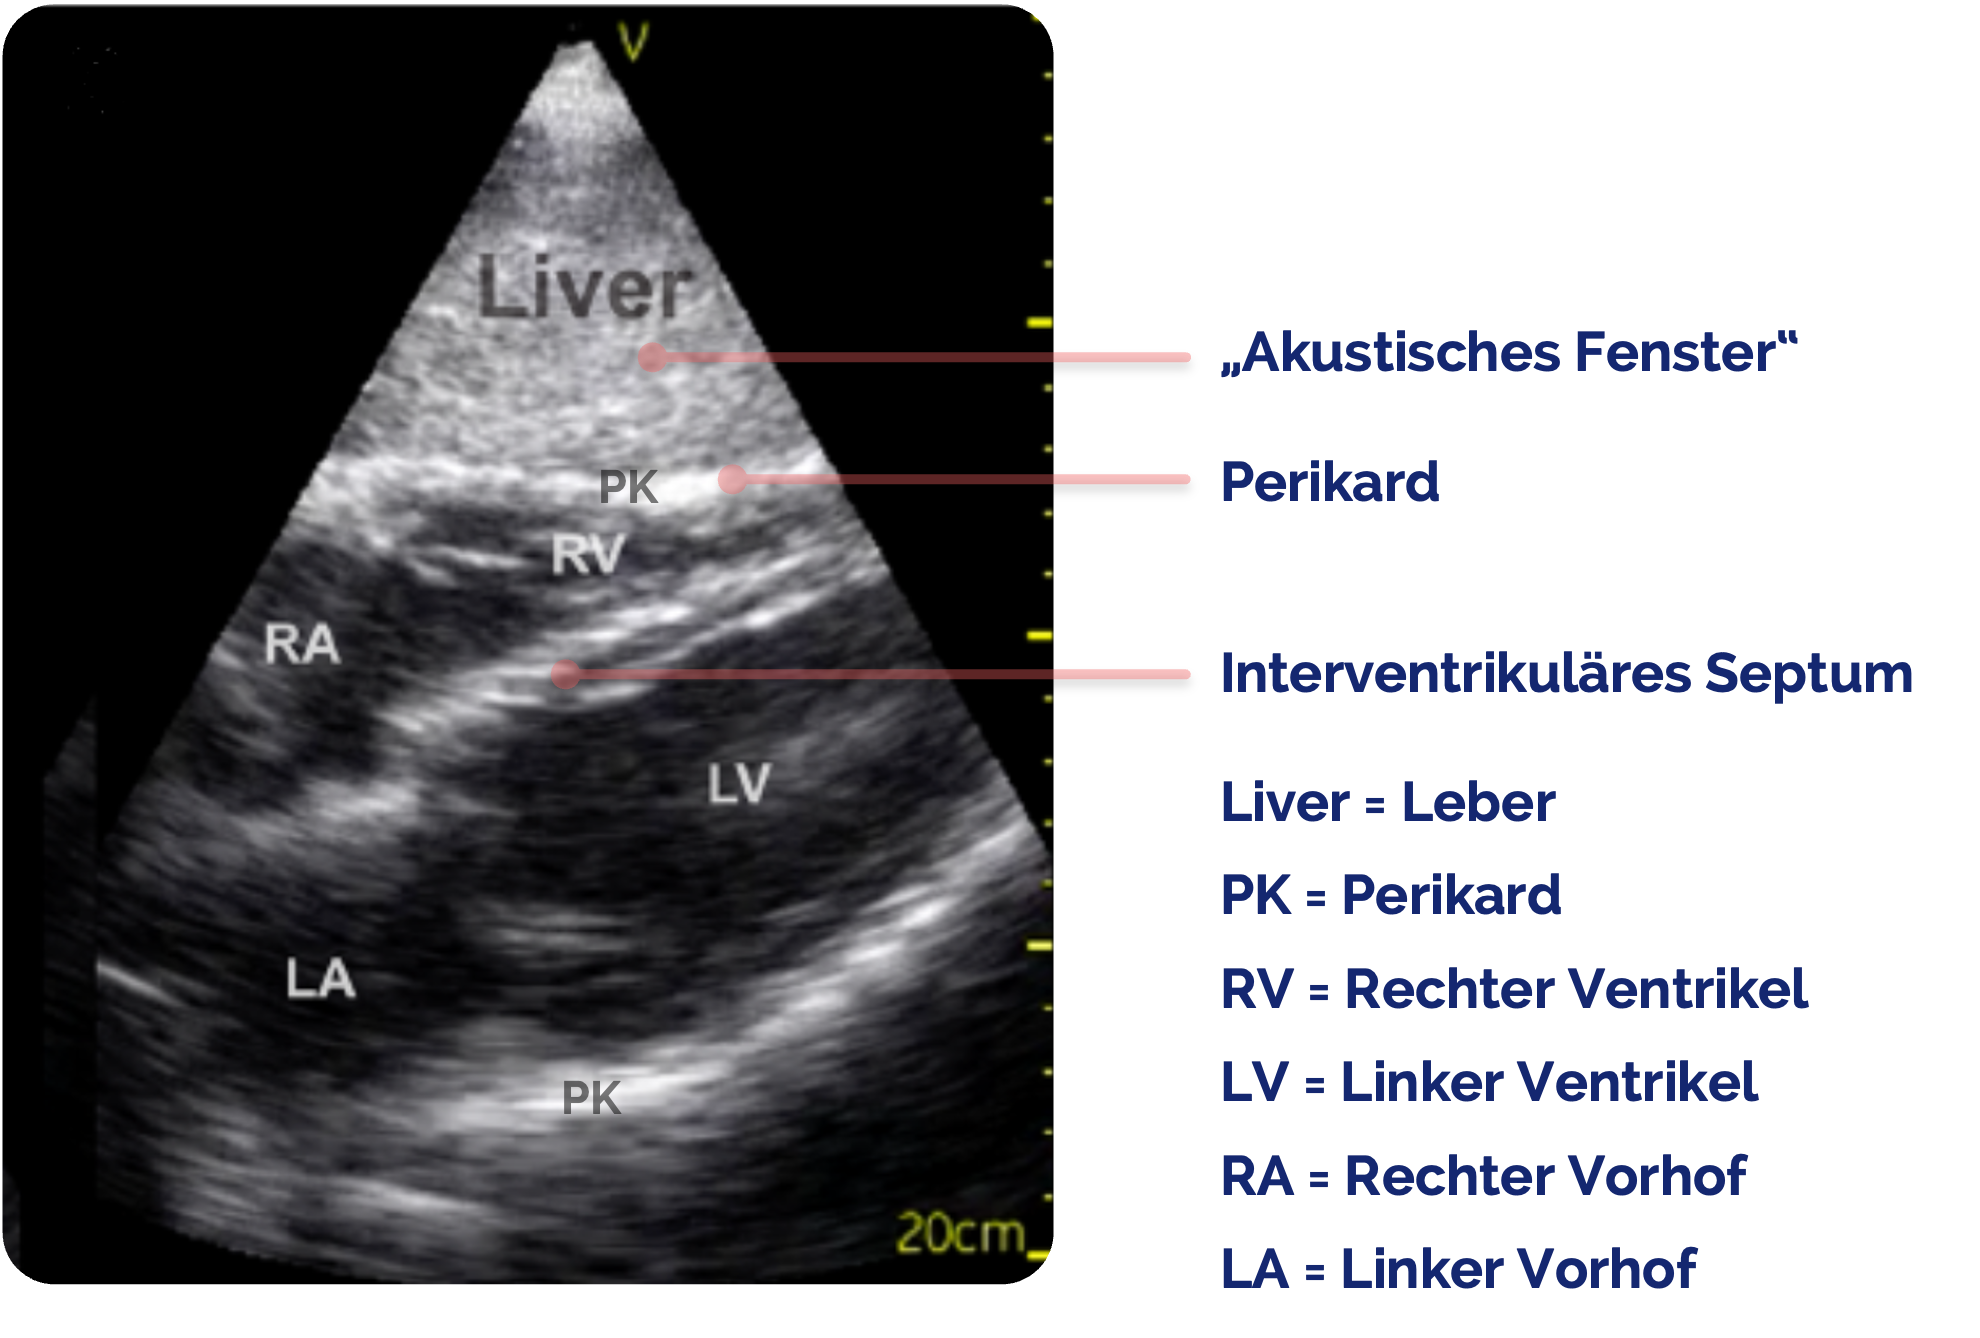

Schritt 2: Strukturorientierung

Figure 1 aus Jakobsen, L.K., Bøtker, M.T., Lawrence, L.P. et al. Systematic training in focused cardiopulmonary ultrasound affects decision-making in the prehospital setting – two case reports. Scand J Trauma Resusc Emerg Med 22, 29 (2014). https://doi.org/10.1186/1757-7241-22-29. Das Bild wurde zugeschnitten und es wurden Markierungen hinzugefügt.

Zunächst sichere Orientierung

- Leber

im Vordergrund (Liver ➜) - Dahinter Zwerchfell

(ZF ➜) - Direkt darüber das Herz, meist beginnend mit dem rechten Atrium (RA ➜) und rechten Ventrikel (RV ➜) und folgend mit dem linken Atrium

(LA ➜) und linken Ventrikel (LV ➜) - Perikard

als echoreiche Linie, die das Herz umgibt (PK➜)

Im subxiphoidalen Schnitt zeigt sich das Herz vollständig in der Vierkammeransicht hinter der echoreichen Linie des Zwerchfells

Im Vordergrund liegt das homogene Parenchym der Leber

Figure 1 aus Jakobsen, L.K., Bøtker, M.T., Lawrence, L.P. et al. Systematic training in focused cardiopulmonary ultrasound affects decision-making in the prehospital setting – two case reports. Scand J Trauma Resusc Emerg Med 22, 29 (2014). https://doi.org/10.1186/1757-7241-22-29. Das Bild wurde zugeschnitten und es wurden Markierungen sowie Beschriftungen hinzugefügt.